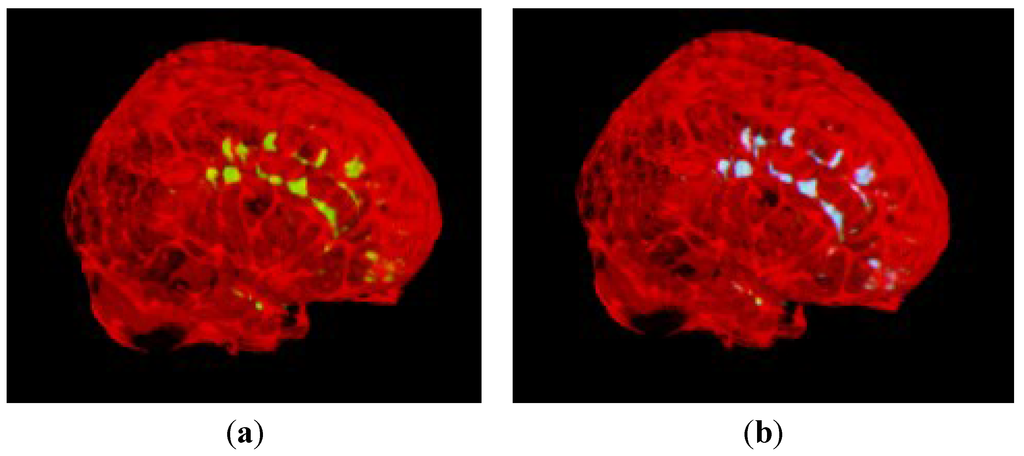

3.2. Segmentation of MS Lesions in a Whole Brain Volume

3.2.1. Brain Data with Mild MS Lesions

3.2.2. Brain Data with Moderate MS Lesions

3.2.3. Brain Data with Severe MS Lesions